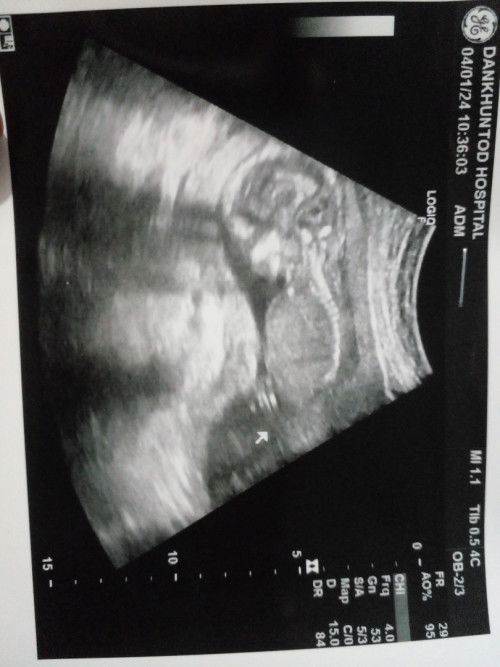

วันนี้ไปพบหมอฟังผลการตรวจ ดาวน์ซินโดรมความเสี่ยงต่ำ และอัลตร้าซาวด์ ปกติดีทุกอย่าง ผลเลือด ไม่จางมาก 33% ตั้งครรภ์ 17 สัปดาห์ 5 วัน น้องน้ำหนัก 190 กรัม #ท้องสามค่ะ